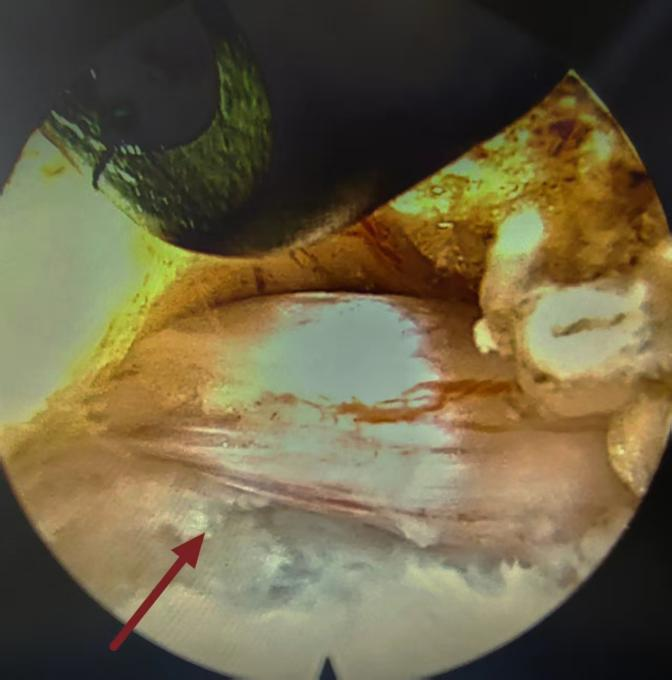

(镜下见脱出间盘压迫神经根)

(摘除间盘后神经根压迫解除)